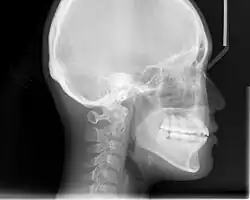

Lateral cephalometric radiographs

Lateral cephalometric radiograph, used for skull analysis

Lateral cephalometric radiograph is a radiograph of the head taken with the x-ray beam perpendicular to the patient's sagittal plane. Natural head position is a standardized orientation of the head that is reproducible for each individual and is used as a means of standardization during analysis of dentofacial morphology both for photos and radiographs. The concept of natural head position was introduced by Coenraad Moorrees and M. R Kean in 1958[9][10] and now is a common method of head orientation for cephalometric radiography.[11][12]